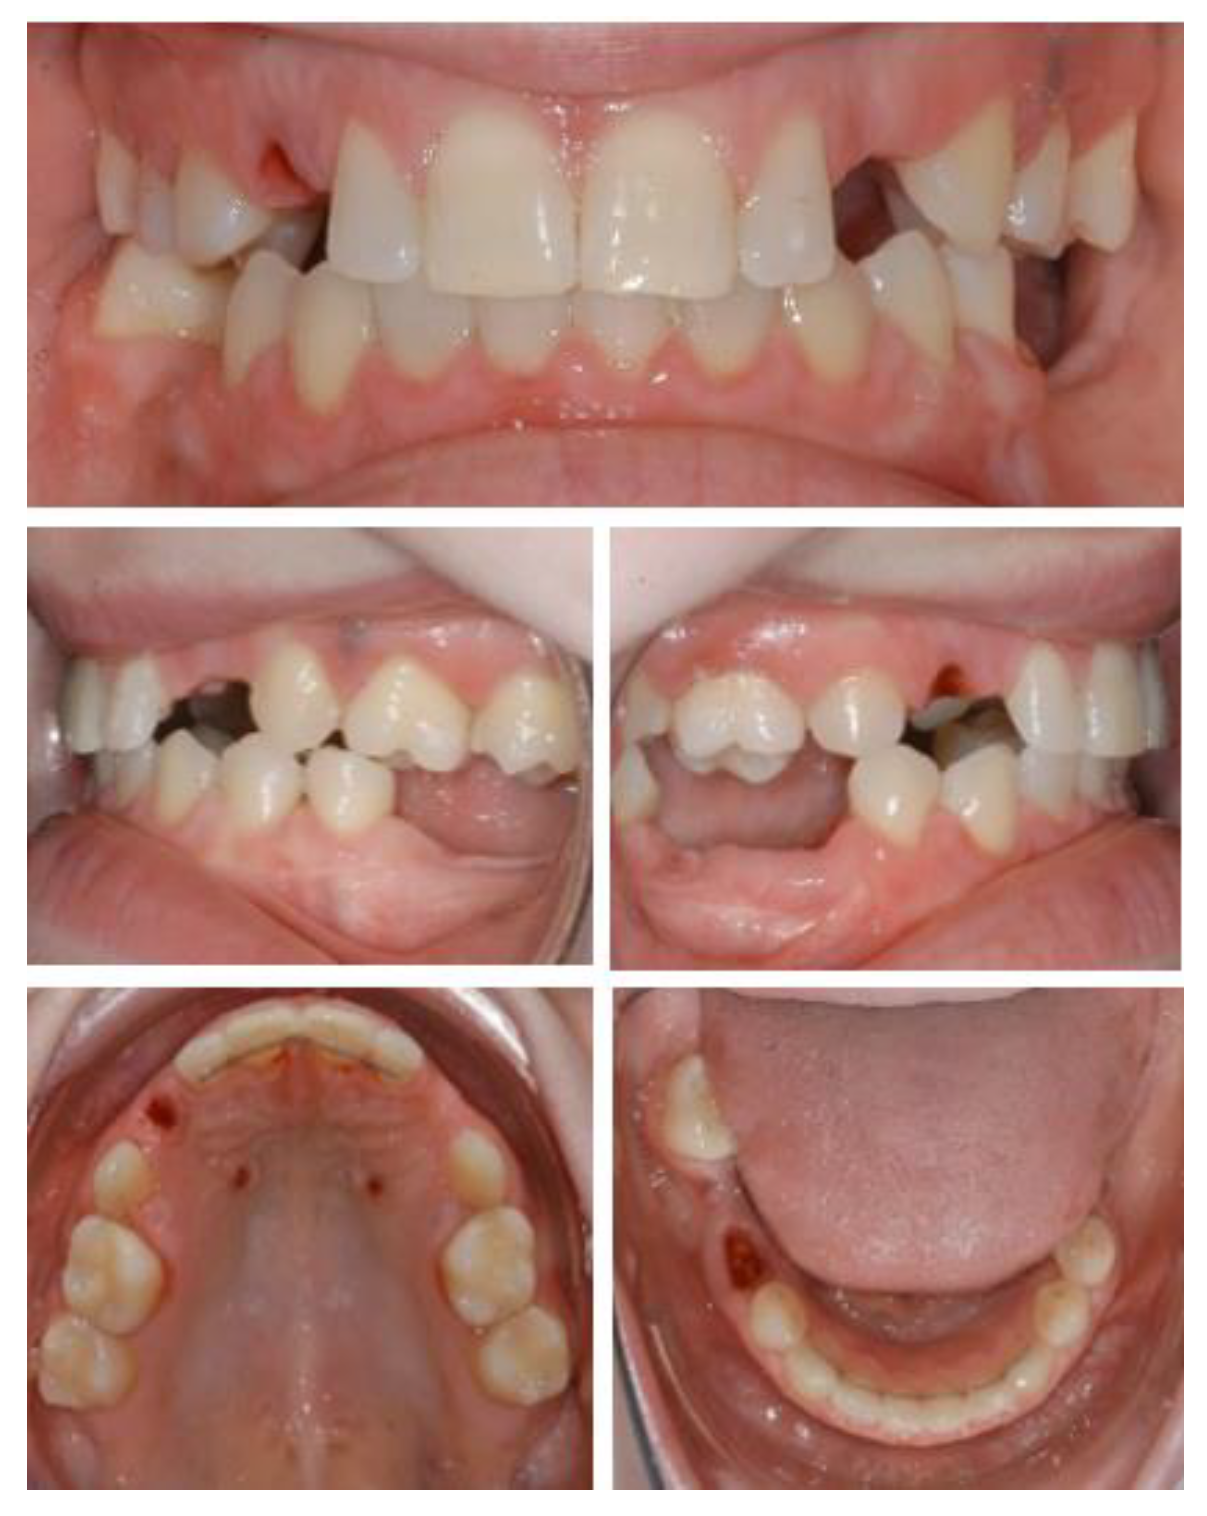

Figure 6.

Intraoral situation after orthodontic treatment and extraction of deciduous teeth.

Figure 7.

Initial panoramic radiography.

A 25-year-old patient attended the Dental Clinic of Hospital University Münster about the unattractive smile and limited function. Anamnesis revealed an ectodermal dysplasia, which was confirmed genetically. No history of medication or allergy was given. Intraoral and radiological examination showed a permanent tooth agenesis, permanence of primary dentition and reduced vertical dimension. The interdisciplinary treatment included presurgical orthodontic treatment for teeth alignment and increase in vertical dimension, coronoplasty of anterior teeth, followed by implant placement at the sites 13, 23, and 25 and rehabilitation with implant-supported crowns.

At the time of implant planning, orthodontic treatment was already finalized. Dental implants were planned to replace missing teeth at sites 13, 23, 36, 45, 46. Despite adequate teeth alignment, wide interproximal spaces at sites 13 and 23 revealed the need of combined restorative and surgical treatments (Figure 6 and Figure 7). Thus, dental implantation in the upper jaws was associated with enlargement of lateral incisors and correction of form in the case of teeth 13, 23.